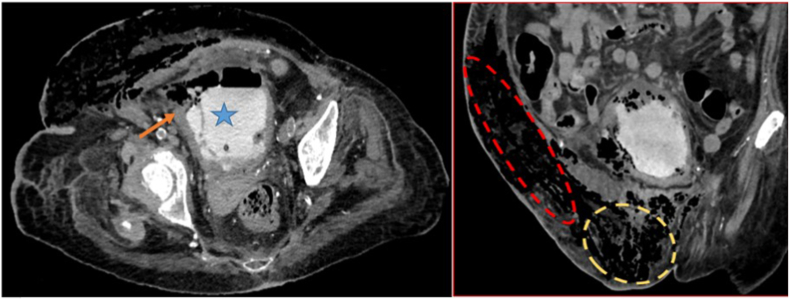

Radiology showed an air-fluid level inside the urinary bladder and extensive gas within the bladder wall and lumen, consistent with emphysematous cystitis. We, as well, found subcutaneous edema extending from the right groin along the right lower abdominal wall with a large amount of subcutaneous gas (Fig. 2). Emphysematous cystitis complicated with necrotizing fasciitis was suspected which requires immediate surgical treatment.

Fig. 2.

CT with cystography findings: urinary bladder (blue star) associated with extensive air within its wall (orange arrow). The red dashed line delimited area shows the subcutaneous gas in the anterior abdominal and the yellow one shows the genital area. (For interpretation of the references to colour in this figure legend, the reader is referred to the Web version of this article.)